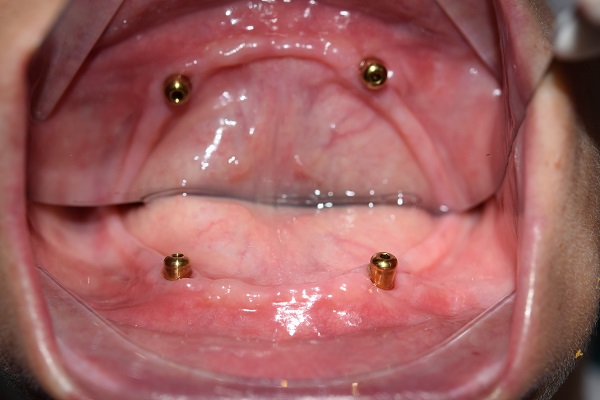

蔡女士坚持只要有一线希望就不会放弃,她说自己会全力配合医生的治疗方案,也能理解相应的并发症及可能不太佳的修复效果。有了患者的充分信任,王主任和傅医生通力合作,先对患者凹凸不平的牙槽骨进行修整并切除过多增生的松软牙龈,根据口腔修复学原理,在CT指示下,在其下颌双侧尖牙区发现两个仅有的可用种植位点,拟采用目前国内外最为先进的种植修复方式,即种植体支持式Locator球帽固位的下颌半口义齿修复下颌牙列缺失。